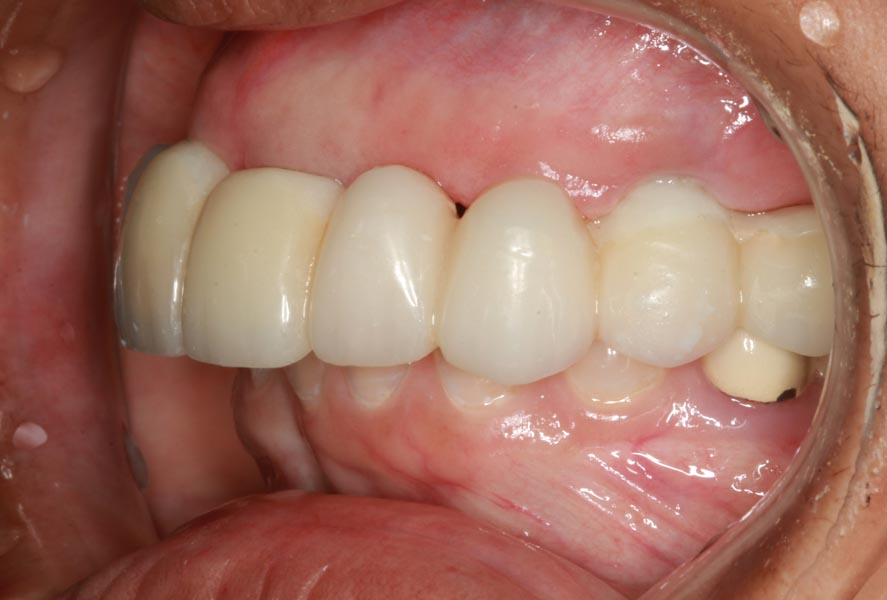

Smile GalleryImplant RestorationsFull Mouth Implant Restoration Full arch zirconia implant bridge (full smile) 1 of 37 Pre-op full smile Pre-op lips retracted Pre-op panoramic x-ray Extraction of strategic teeth Placement of implants Extraction of some remaining teeth after verification of adequate implant stability Occlusal view Post-op panoramic x-ray Immediately fabricated provisional restoration (tissue side view) Immediately fabricated provisional restoration (occlusal side view) Immediate provisional delivered on day of surgery Immediate provisional 2 weeks later Scalloped tissue developed from the provisional at 2 weeks Jig used for making a master impression Provisional in place (full smile) Provisional in place (lips retracted) Provisional in place (right side) Provisional in place (left side) Wax try-in (full smile) Wax try-in (right side full smile) Wax try-in (left side full smile) Wax try-in (full face, lips together) Wax try-in (full smile) Wax try-in (right side) Wax try-in (left side) Wax try-in (lips retracted) Full arch zirconia implant bridge on master cast (frontal view) Full arch zirconia implant bridge on master cast (occlusal view) Implant positions and soft tissue representation on master cast (occlusal view) Soft tissue representation on master cast (frontal view) Full arch zirconia implant bridge (tissue side view) Soft tissues on day of delivery (occlusal view) Soft tissues on day of delivery (frontal view) Full arch zirconia implant bridge delivered (lips retracted) Full arch zirconia implant bridge (lips retracted, close up) Post treatment panoramic x-ray Full arch zirconia implant bridge (full smile)